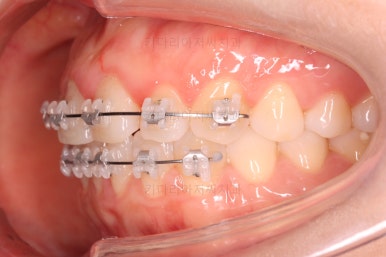

부산나비앞니교정 키다리아저씨치과에 처음 내원하셨을 당시의 입 안 모습입ㄴ디ㅏ.

보시다시피 위아래 정중앙에 있는 치아가 V자 형태로 꺾여있었어요.

흔히 "나비치아", "나비앞니"라고 표현을 하는데 나비 날개짓을 하듯이 꺾여 있다고 그렇게 부릅니다.

장치 부착 시점의 사진입니다.

장치를 붙이고 철사가 구불구불 들어가게 되면 그제서야 "이렇게 많이 틀어져 있었구나"를 더 잘 느 끼시게 됩니다.

이번에 사용한 장치는 엠파워 클리어라고 하는 자가결찰 세라믹 장치인데 같은 계열로는 엠파워 클리어를 비롯해 클리피씨 등이 있어요.

치아에 붙는 장치가 치아색과 비슷한 세라믹으로 만들어져 있고 철사를 붙잡아 주는 클립이 달려 있어 스스로 철사를 묶을 수 있다고 해서 "자가결차" 이라고 표현해요.